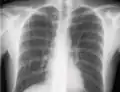

If a pneumothorax is suspected, an upright chest x-ray should be obtained. An upright chest x-ray is preferred because free air will migrate to the apex of the lung, where it is easily visualized. Of course, this is not always possible, particularly in critically ill patients in the intensive care unit. Radiographs obtained in the supine position fail to detect 25–50% of pneumothoraces.[6] Instead, bedside ultrasound is a superior method of detection in those too ill to obtain upright imaging.[3]

During subclavian vein central line placement, the catheter can be accidentally pushed into the internal jugular vein on the same side instead of the superior vena cava. A chest x-ray is performed after insertion to rule out this possibility.[26] The tip of the catheter can also be misdirected into the contralateral (opposite side) subclavian vein in the neck, rather than into the superior vena cava.

The line is then inserted using the Seldinger technique: a blunt guidewire is passed through the needle, then the needle is removed. A dilating device may be passed over the guidewire to expand the tract. Finally, the central line itself is then passed over the guidewire, which is then removed. All the lumens of the line are aspirated (to ensure that they are all positioned inside the vein) and flushed with either saline or heparin.[1] A chest X-ray may be performed afterwards to confirm that the line is positioned inside the superior vena cava and no pneumothorax was caused inadvertently. On anteroposterior X-rays, a catheter tip between 55 and 29 mm below the level of the carina is regarded as acceptable placement.[37] Electromagnetic tracking can be used to verify tip placement and provide guidance during insertion, obviating the need for the X-ray afterwards.